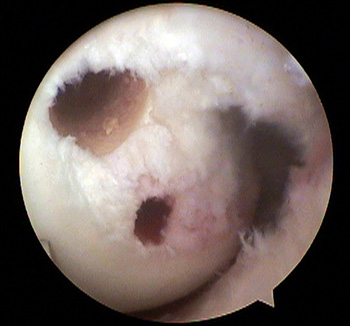

maestu1_fig3

Figura 3: vista artroscópica desde portal anterolateral del túnel anterolateral y marcado del túnel posteromedial en una rodilla izquierda.

maestu1_fig4

Figura 4: vista artroscópica desde portal anterolateral de túneles femorales para bandas anterolateral y posteromedial en una rodilla izquierda.